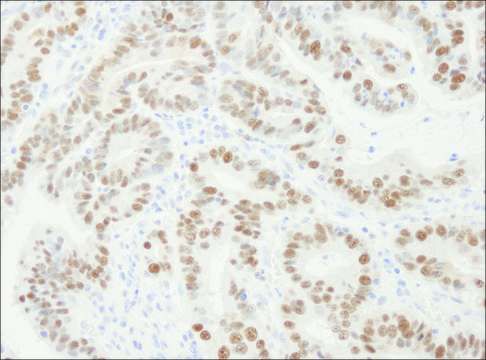

immunohistochemistry: 1:2,000- 1:10,000

Proliferating cell nuclear antigen (PCNA), a single-copy gene, spans about 12 kb. This gene is located on human chromosome 20p13. PCNA is expressed at high levels in the thymus, bone marrow, fetal liver, and some cells of the small intestine and colon. It is located in the nucleus.

The epitope recognized by PLA0079 maps to a region between residues 75 and 125 of human proliferating cell nuclear antigen using the numbering given in SwissProt entry P12004 (GeneID 5111).